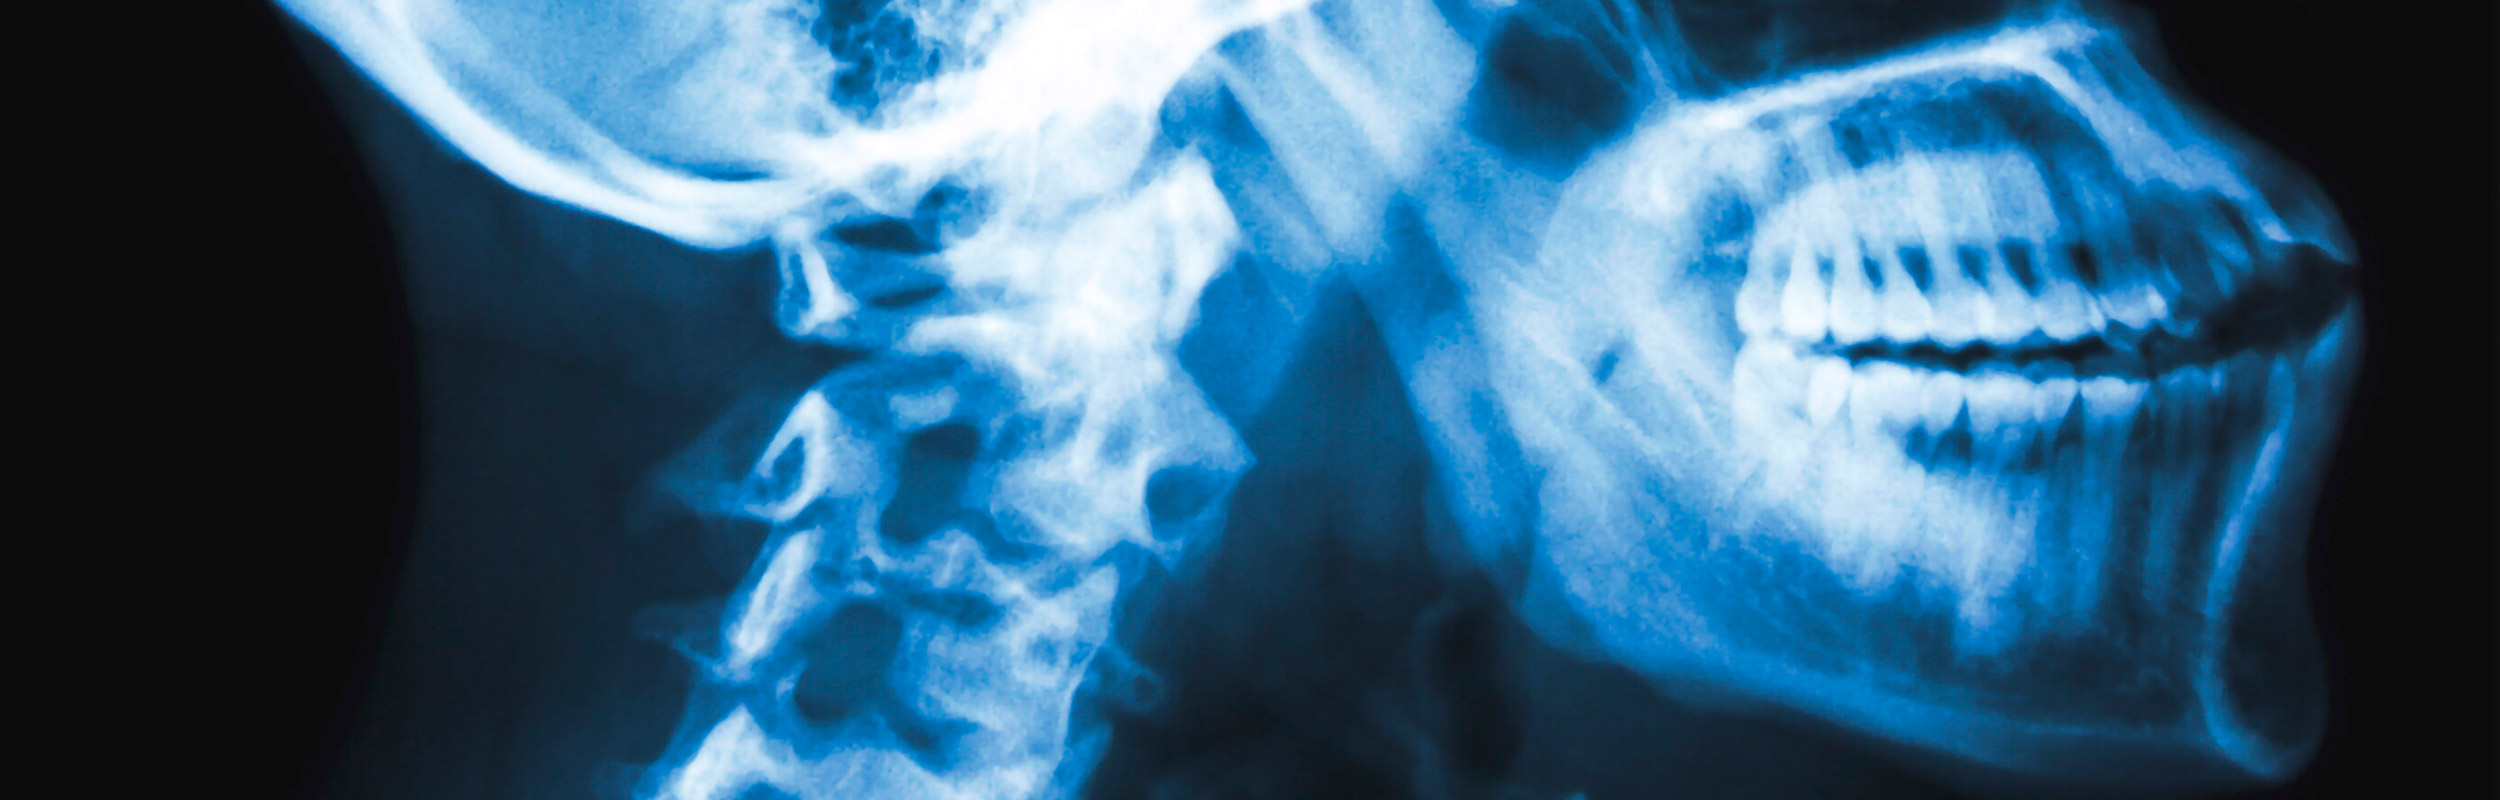

Facharzt für Orthopädie mit mehr als 5000 operativen Eingriffen und Präsident der Österreichischen Gesellschaft für Wirbelsäulen-Chirurgie.

Dr. Bach ist seit 2001 habilitierter Facharzt für Orthopädie und Spezialist für alle Erkrankungen am Bewegungsapparat. Die Schwerpunkte des Wirbelsäulenchirurgen liegen auf dem Gebiet der Wirbelsäulenerkrankungen und der Endoprothetik, der Implantation künstlicher Gelenke.